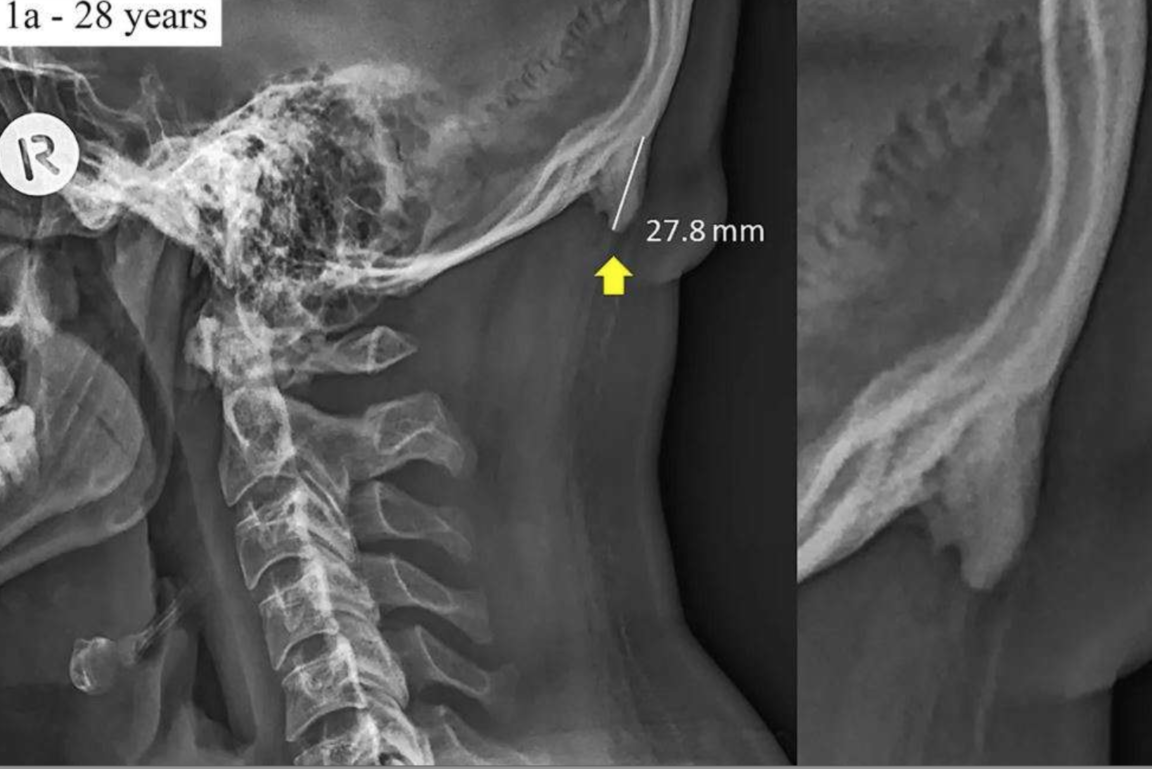

Prenez vos doigts et placez-les à l’arrière de votre crâne, juste au-dessus de la nuque. Si vous sentez une petite croissance osseuse, cela pourrait être le signe que votre corps réagit à une surutilisation des smartphones. C’est en tout cas l’idée proposée suite à la publication d’une récente étude parue dans Scientific Reports, qui relève en effet que de plus en plus de personnes semblent présenter ce type de structures dépassant de l’arrière du crâne. Celles-ci mesurent en moyenne 2,6 cm de long, mais peuvent atteindre 3,1 cm de long chez certains individus.

Cette « protubérance occipitale externe » (EEOP) – relativement rare dans la littérature médicale – devrait normalement mettre plusieurs décennies à pousser. C’est pourquoi, au départ, les chercheurs sont partis dans l’idée qu’elle serait le plus souvent observée chez les personnes plus vieillissantes. Or, ce n’est pas le cas. Dans cette étude portant sur 1 200 personnes âgées de 18 à 86 ans, 33 % des participants présentaient cette croissance osseuse, et tous avaient entre 18 et 30 ans. Les chercheurs ont par ailleurs noté que chaque décennie d’augmentation de l’âge observait une réduction du risque de croissance.